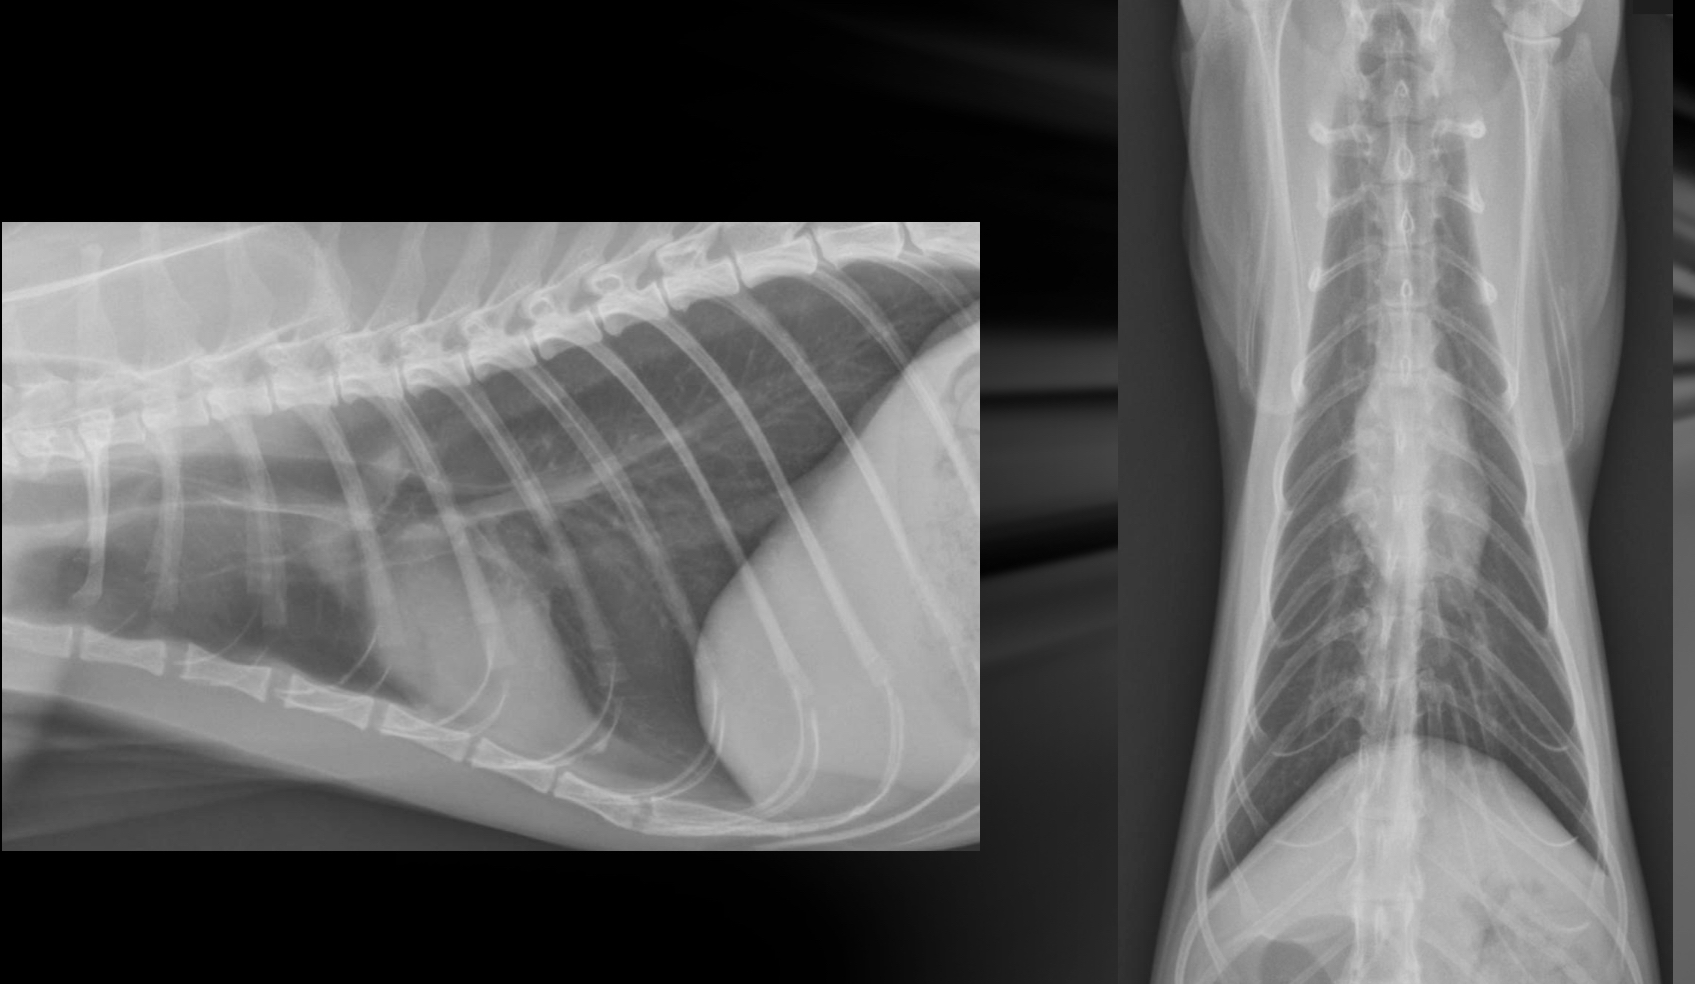

Feline cardiac silhouette and sizing on VD and lateral views

-almond shape

Lat view

-2/3 thoracic height

-2-2.5 IC spaces wide

-trachea deviates from spine

VD

-apex slightly left of midline

-broad convexity in area of right atrium and left ventricle

-flat left auricle area

What is going on with this cat heart?

Microcardia